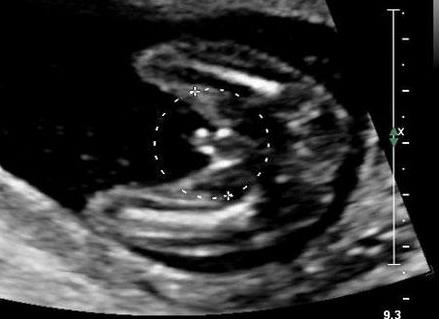

24 недели — УЗИ показывает девочку:

На 12 неделе женщина проходит первое обследование, которое назначается для оценивания зрелости матки, степени развития плаценты, плода. На данном сроке непросто определить пол ребенка, потому что он чересчур мал, и врачу трудно рассмотреть на мониторе его половые органы. Поэтому нередки ошибки УЗИ при определении пола малыша.

Ультразвуковым исследованием можно получить достоверную информацию на диагностике, проведенной с 18 по 22 недели внутриутробного развития плода. До 15 недель беременности вероятность получения достоверной информации минимальна.

Обычно на 21 неделе УЗИ дает более точные результаты. Если у плода удобное положение для проведения диагностики, он не прикрывает гениталии ручками, не шевелит пуповину, то врач может внимательно рассмотреть пол еще не родившегося малыша.